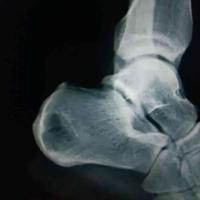

跟骨脂肪瘤,中央亮点为脂肪瘤钙化

跟骨脂肪瘤,中央亮点为脂肪瘤钙化...